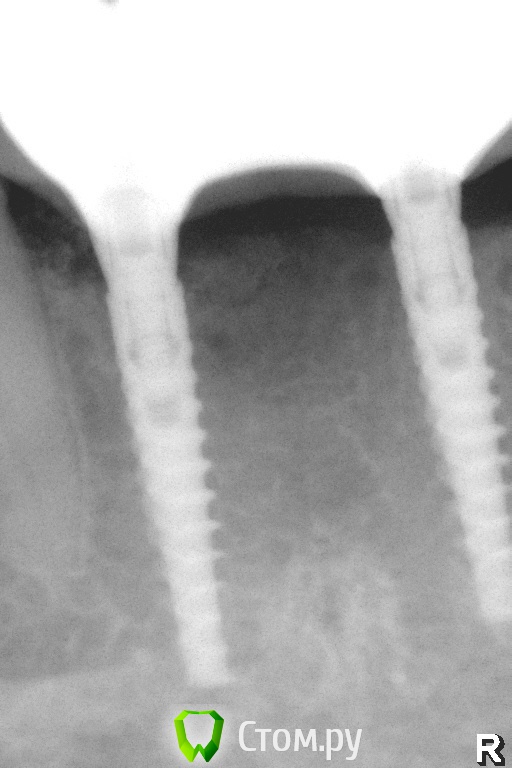

Pavel-Pskov Опубликовано 4 ноября, 2014 Автор Поделиться Опубликовано 4 ноября, 2014 Еще пара снимков.Через год. Ссылка на комментарий

АнтонТЛТ Опубликовано 4 ноября, 2014 Поделиться Опубликовано 4 ноября, 2014 Какие-то странные абатменты, как-будто в имплантаты заходят на 1мм. Ссылка на комментарий

АнтонТЛТ Опубликовано 4 ноября, 2014 Поделиться Опубликовано 4 ноября, 2014 в стартовом сообщении абатменты нормальныеНу там другой кейс)На втором, как будто один трансфер не по размеру у среднего имплантата, конуса не видно просто фаска-углубление. Там не видно и переключения платформы у трансфера.А если сравнивать абатмент у дистального и мезиальных имплантатов, то разница видна Ссылка на комментарий

Pavel-Pskov Опубликовано 6 ноября, 2014 Автор Поделиться Опубликовано 6 ноября, 2014 Ну там другой кейс)На втором, как будто один трансфер не по размеру у среднего имплантата, конуса не видно просто фаска-углубление. Там не видно и переключения платформы у трансфера.А если сравнивать абатмент у дистального и мезиальных имплантатов, то разница виднаДистальный 3,8. Ссылка на комментарий